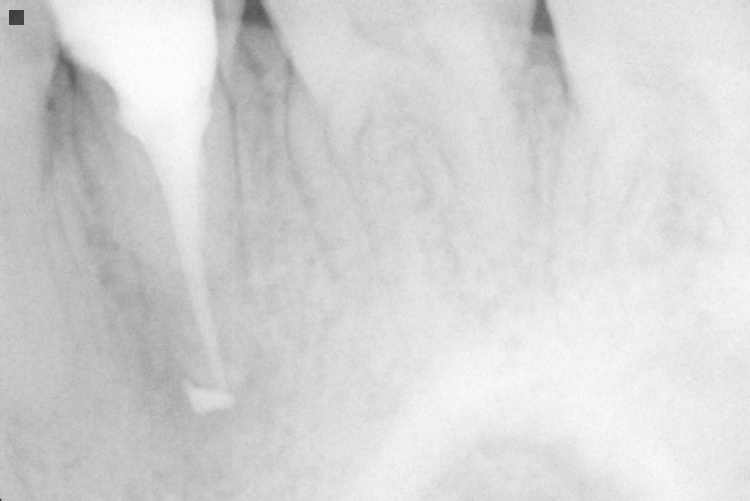

Name Last modified Size Description Parent Directory - IO000001.jpg 2020-07-28 14:17 78K IO000002.jpg 2020-07-28 14:17 78K IO000003.jpg 2020-07-28 14:17 81K IO000004.jpg 2020-07-28 14:17 76K